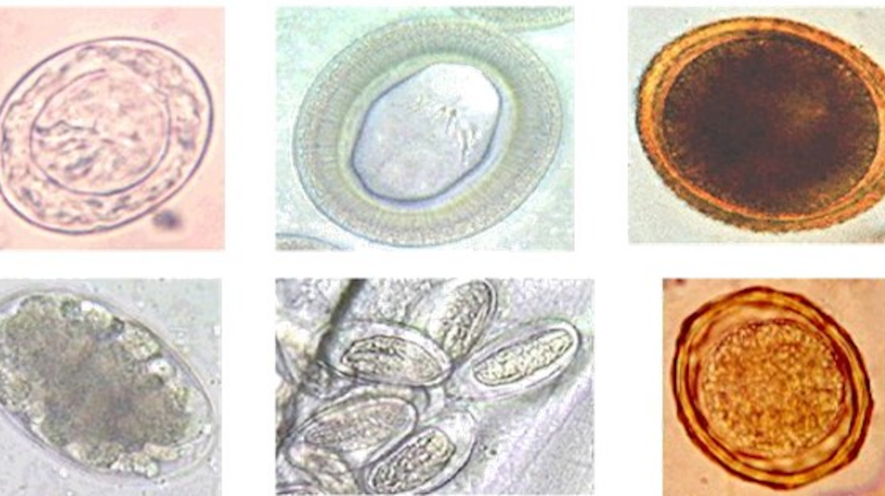

Микрофотографии яиц гельминтов Toxocara canis

Раздел: Фотоэссе